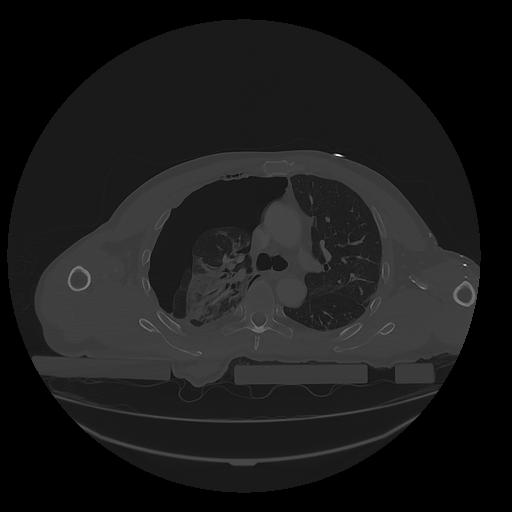

31 PULMON,CE,Vol,1.0,PULMON,,